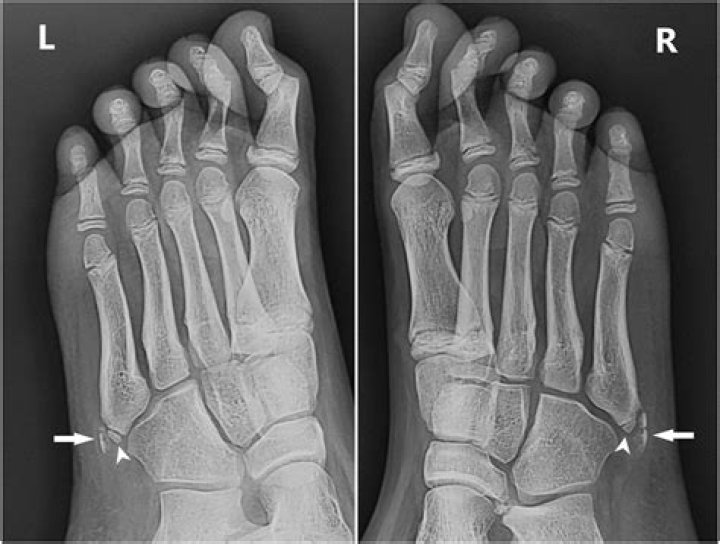

Is there a growth plate at the base of the 5th metatarsal?

Iselin disease is painful inflammation of the apophysis (growth plate) at the base of the 5th metatarsal (foot bone). The growth plate is made up of cartilage, which is softer and more vulnerable to injury than mature bone.

What age does 5th metatarsal apophysis fuse?

Apophysis of the fifth metatarsal base appears on radiographs at age 10 for girls, and age 12 for boys. Fusion of the apophysis and the fifth metatarsal base usually takes place within the following 2–4 years.